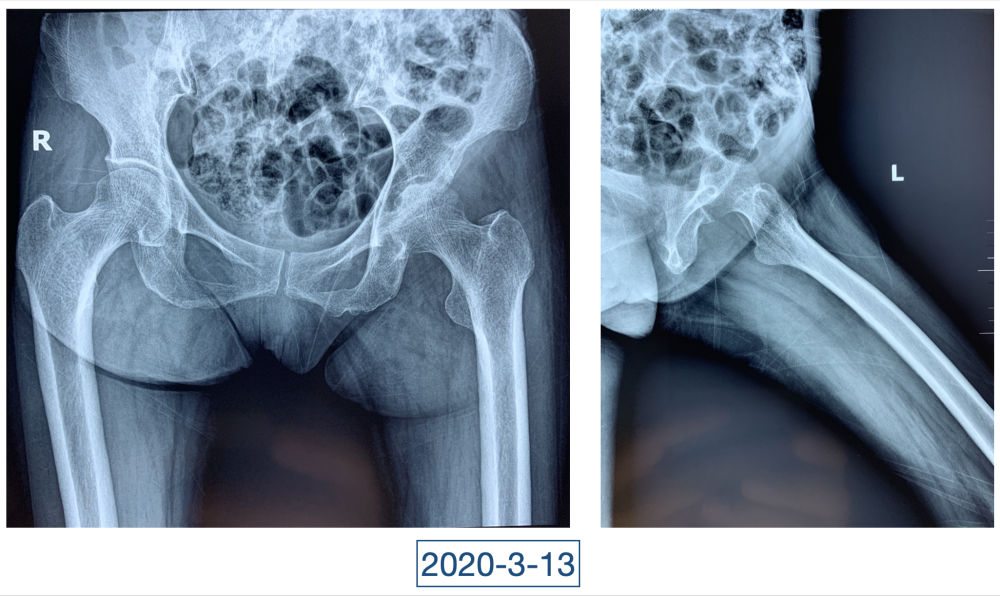

“虽说没到奄奄一息的地步,但一看就是患了大病,整个人都瘦脱相了。”李辉是西安市红会医院关节病医院病区副主任,2020年4月初第一次见到黄大娘时,他吓了一跳。黄大娘今年61岁,2019年腊月二十九,在家打扫卫生准备迎接新年的她突然开始高烧不退,腰背也痛。连夜送到当地医院补液、止疼、退烧、抗感染,一套组合拳下来烧是退了,疼痛的症状却持续在加重。从过年到正月,一直在当地医院输液、打针,黄大娘都没有好转,疼痛的地方反而越来越多。大概过半月,就多一个地方,腰、背、胸、颈部、关节、脚……此起彼伏,全身上下都觉得疼痛无比。哪里疼就去哪个科,今年四月前,黄大娘辗转多家医院多个科室寻求治疗,住院出院了一次又一次,连最高级别的抗生素都用到了,但就是没有效果。

一直到了四月,因为髋关节疼痛的原因,她又来到红会医院关节病医院。李辉见到的黄大娘是坐着轮椅的,家里人说她已经到了卧床不起的地步,原本近107斤的人只用了3个月时间就瘦到了34斤。“这是患上了什么大病,才能让人变成这个样子?”看着憔悴不堪,可以用皮包骨头来形容的黄大娘,李辉心里一沉,担心起来。

全身上下11处骨关节被破坏!密密麻麻的诊断看得李辉毫无思绪,这么久都查不出来的病因能让他查出来吗?一时间,他也说不出话。看着黄大娘深深凹陷的双眼,浑身上下几乎看不见肉,就像罩着一层饥饿的青黄色的薄皮。过了好一会儿,他叹了口气,说:“先住下吧,用药把关节疼痛缓解一下,再想办法。”

经过科室讨论、会诊,李辉也查阅了很多资料,按照黄大娘的症状,他跟之前的接诊医生一样,觉得应该是骨关节感染。可之前的穿刺、培养各种检查也做过,为什么没有找到致病菌?李辉想,或许是检查中出现了问题,没有查对地方。于是他决定,在B超引导下骨穿刺,通过最新技术精准定位病灶,只有这样也许才能抓到真正的“罪犯”。

在黄大娘入院第四天,李辉将她推入检查室,结果很快出来了,为烟曲霉菌感染。这个结果验证了李辉的想法,也解释了此前抗感染药物为何一直不奏效。“找到元凶就好办了,对症用药就可以。真菌感染本来治疗时间就很长,骨科类感染灶治疗时间更长,用了5个月的时间,终于治好了。”

近日随访得知黄大娘身体好转,李辉脸上的笑容掩饰不住,他说,据查阅文献,11处感染灶,这是全世界感染灶最多的骨关节感染,但现在,这罕见、复杂的病已经被治愈。